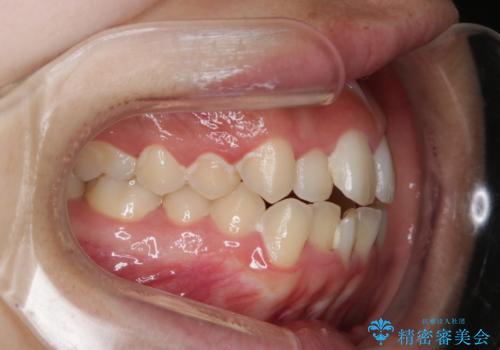

オープンバイト(開咬)を非抜歯インビザラインで治す

- 上下のがたつきを気にされてご相談にいらした患者さまです。

症状としてはオープンバイト(開咬)があり、舌癖も見られました。

オープンバイトの方への治療は、通常抜歯を行いワイヤーによる矯正治療を行うことが多いですが、今回はインビザラインの特性を生かし、非抜歯にて綺麗な歯並びを作ることが出来ました。